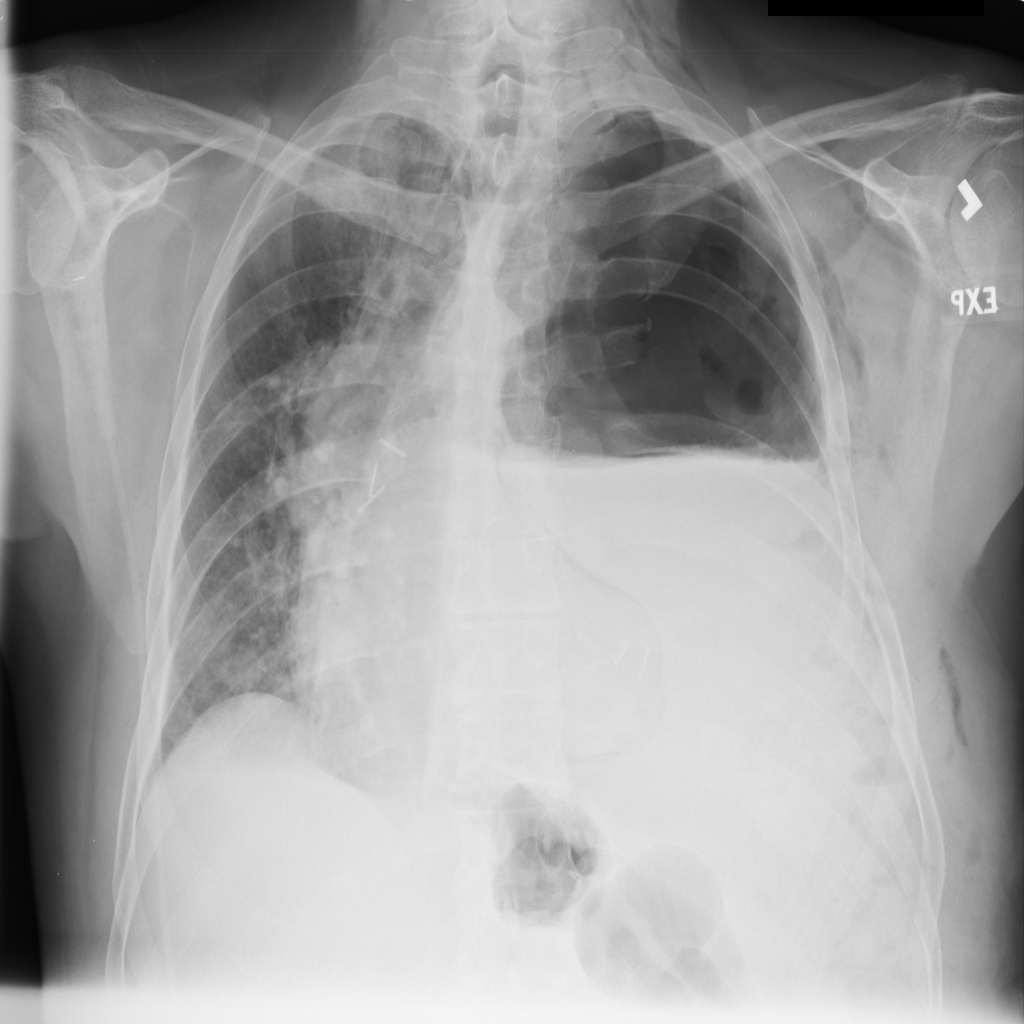

PAT-B0DB · IMG-003Emphysema

PAT-B0DB · IMG-003

PA